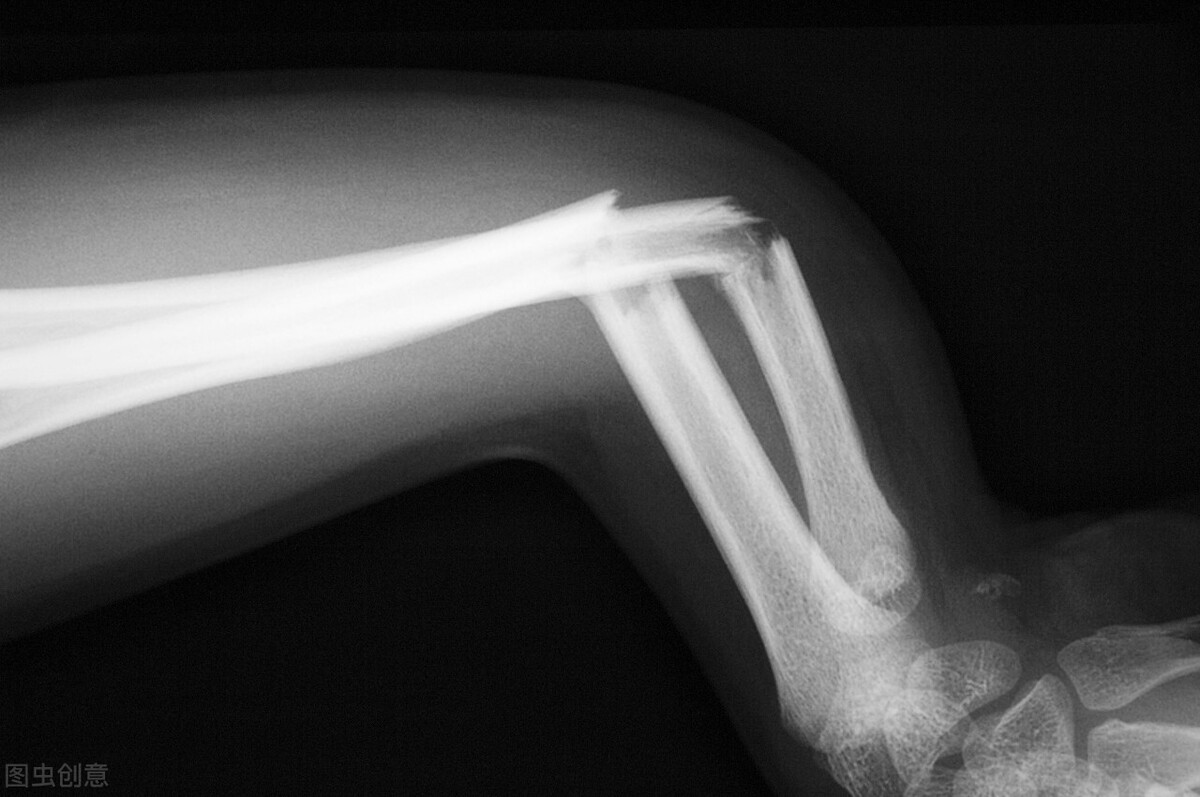

从X摄片上我们可以看到,骨头上处处是虫噬样的小洞,骨结构被破坏,只需要轻轻的力量,骨折就发生了。

有一类骨折,很蹊跷。没有明显暴力就骨折了。比如伸了一个懒腰骨折了,打了一个喷嚏骨折了,走路滑了一下大腿骨折了,骑自行车等红灯腿撑地时就骨折了。这一类骨折就不单纯了,要加倍小心,有可能是骨肿瘤导致的病理性骨折。